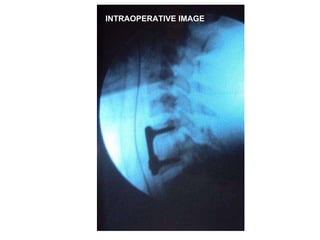

Results  MRI scans in all patients Early operation in majority No intra-operative complications Safe operations with minimum equipment 2 patients were irreducible

Irreducible dislocation but cord well decompressed

INTRAOPERATIVE IMAGE

Results MRIscans in all patients Early operation in majority No intra-operative complications Safe operations with minimum equipment 2 patients were irreducible

Irreducible dislocation butcord well decompressed